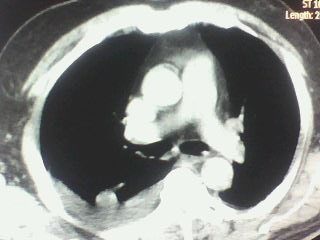

以下是引用随光逐影在2009-9-26 22:31:00的发言:[br]支持 右肺中叶炎症,双侧胸腔积液伴右肺下叶膨胀不全;急性胆囊炎,右肾囊肿,腹水,右侧肾周筋膜增厚。

以下是引用zjzjr在2009-9-26 22:28:00的发言:[br]右肺中叶炎症,急性胆囊炎,双侧胸腔积液伴右肺下叶膨胀不全,腹水,右肾囊肿.右侧肾周筋膜增厚.